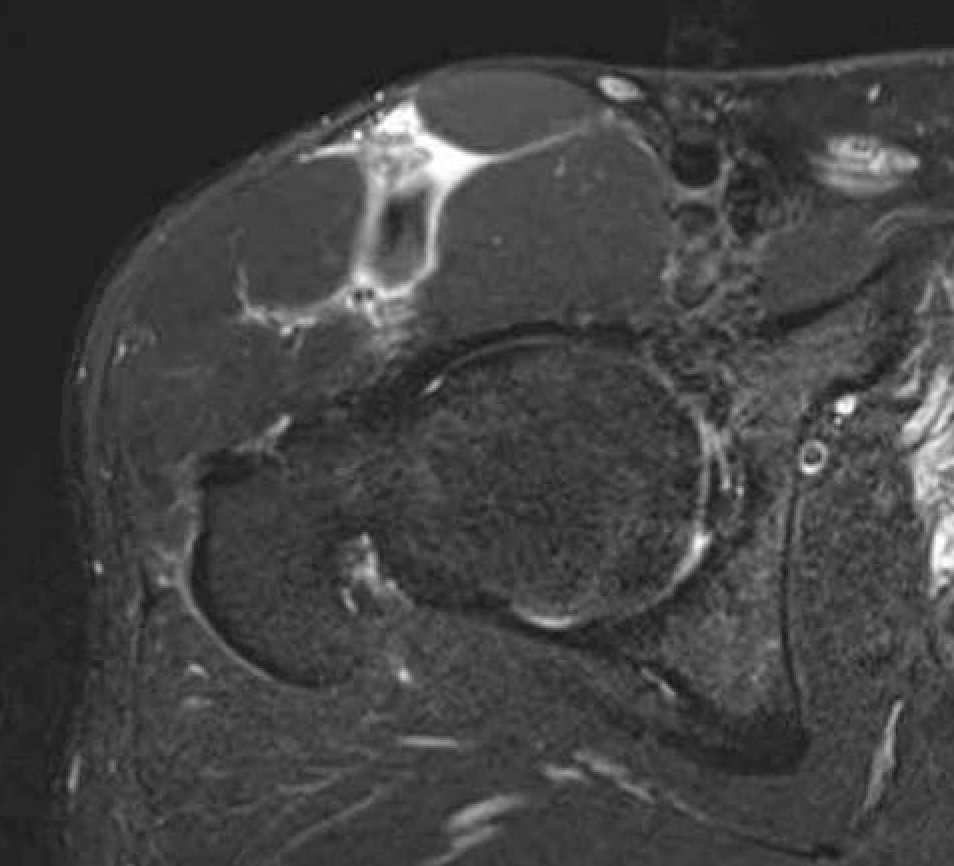

Grade 4C direct head MTPJ rectus femoris